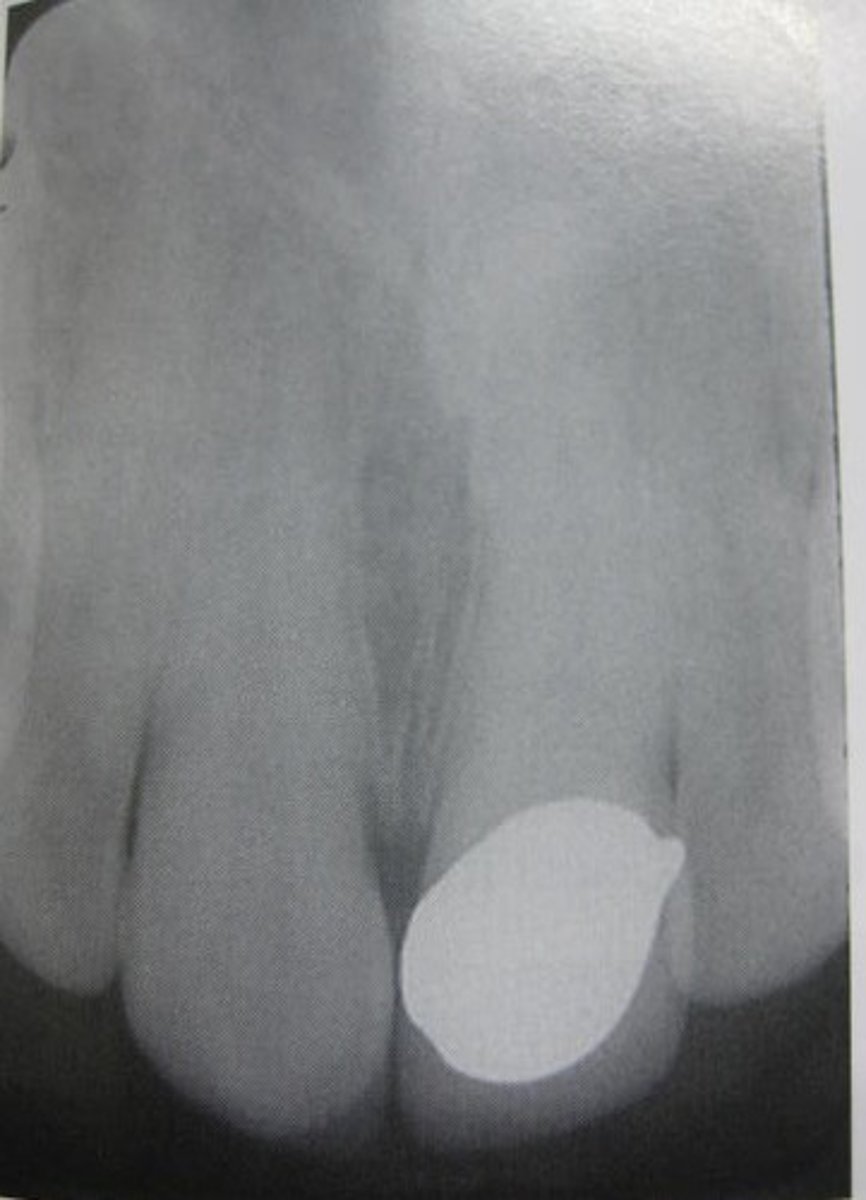

what is used to fill root canals?

gutta percha (zinc oxide)

silver point

radiopaque